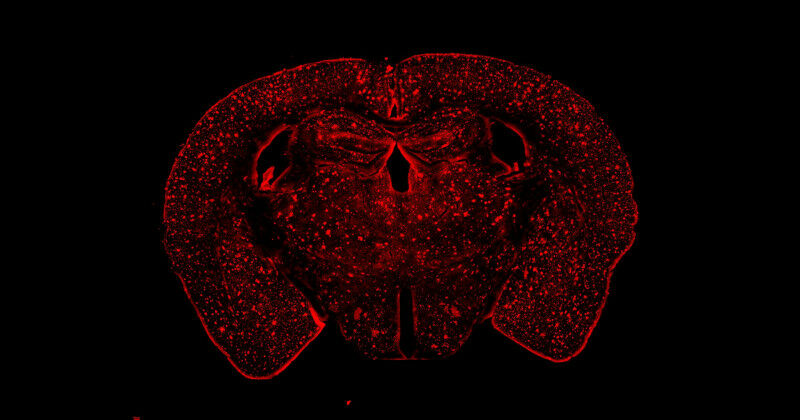

Brain plaques of mouse models in Alzheimer’s disease show beta-amyloid protein buildup in the form of bright spots across the brain. (Schulich School of Medicine & Dentistry image)

Brain plaques of mouse models in Alzheimer's disease show beta-amyloid protein buildup in the form of bright spots across the brain. (Schulich School of Medicine & Dentistry image) Western researchers reveal link between Alzheimer's disease and sex hormones Use of female animal models in the lab led to crucial finding Alzheimer's disease disproportionately affects women, who represent about two-thirds of those diagnosed with the late-onset type of the disease. Previous research has shown Alzheimer's is also more severe and progresses more rapidly in women, and women with Alzheimer's experience a steeper cognitive decline - loss of memory, attention, and the ability to communicate and make decisions - compared to men with the disease. The biological bases for these differences between men and women with Alzheimer's disease are not well understood. However, understanding them is necessary for developing appropriate therapies. In a new study in mice and humans, Western researchers have shown female sex hormones play a significant role in how Alzheimer's manifests in the brain. The study, published in Alzheimer's & Dementia: The Journal of the Alzheimer's Association , also highlights the importance of developing therapeutic strategies focused on these hormonal connections.